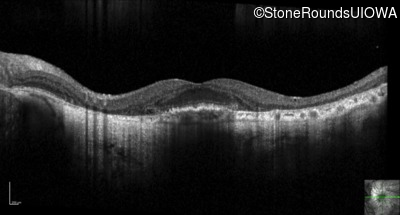

Optical Coherence Tomography - Right - 20/125

Exemplar / OCT Stack